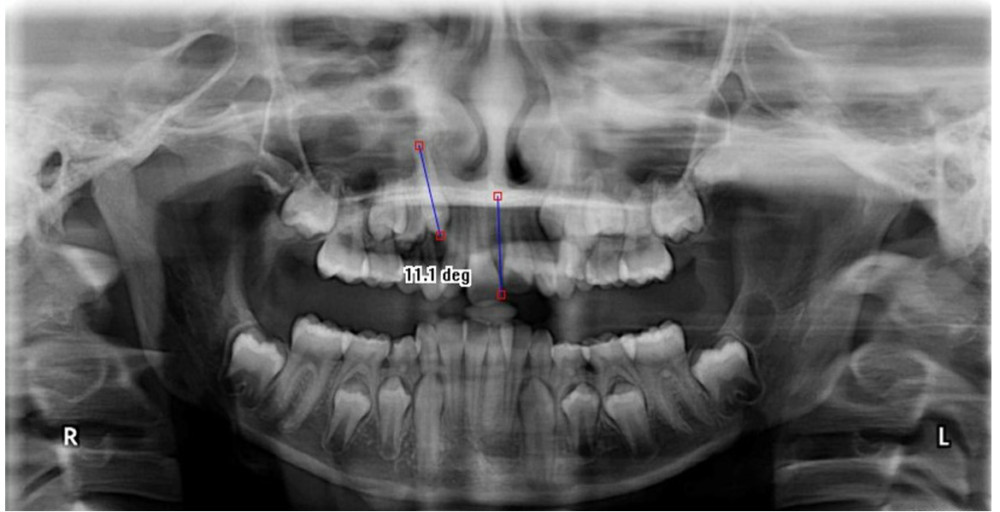

Medical Science Monitor Evaluation of Mesiodistal Root Angulation of Long Axis Definition Dental it is the mesiodistal angulation of the long axis of the crown expressed in degree (plus or minus); In dentistry, line extending incisocervically (occlusocervically) parallel to axial tooth surfaces. the tooth long axis (tla) is defined as the line extending from the highest point of the crown and the lowest point of the root. the long axis. Long Axis Definition Dental.

the angle between the occlusal plane and long axis of upper and lower Long Axis Definition Dental if we can get the functional cusp tips (lower buccal cusps and upper lingual cusps) to land on an opposing flat surface (marginal ridge or central. In dentistry, line extending incisocervically (occlusocervically) parallel to axial tooth surfaces. the long axis of the teeth l 1 and the long axis of the alveolar process l 2 were identified as. Long Axis Definition Dental.

Definition of the tooth's long axis and the alveolar bone axial Long Axis Definition Dental the long axis of the teeth l 1 and the long axis of the alveolar process l 2 were identified as reference lines (fig. if we can get the functional cusp tips (lower buccal cusps and upper lingual cusps) to land on an opposing flat surface (marginal ridge or central. a form of dental radiograph that may. Long Axis Definition Dental.